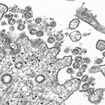

- This virus is not a living organism. It is a protein molecule (RNA or DNA) covered by a protective layer of lipid (fat), which, when absorbed by the cells of the ocular (eyes), nasal (nose) or buccal mucosa (mouth), changes their genetic code (mutates) and converts into aggressor and multiplier cells.

- Since the virus is not a living organism, but is a protein molecule, it cannot be killed. It has to decay on its own. The disintegration time depends on the temperature, humidity and type of material where it lies.

- The virus is very fragile; the only thing that protects it is a thin outer layer of fat and that is the reason why soap or detergent is the best weapon. The foam CUTS THE FAT (that is why you have to scrub for 20 seconds or more, to create lots of foam). By dissolving the fat layer, the protein molecule disperses and breaks down.